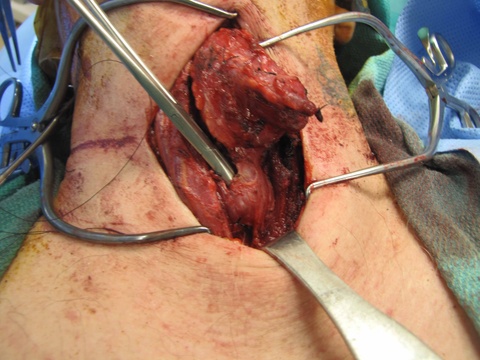

The patient was then prepped (including 1010 drape) and positioned for a central neck dissection thyroglossal duct cyst removal. Just to the left of midline, a large mass was palpated. A 15 blade was used to incise the skin with a horizontal marked incision and down onto the mass. Subplatysmal flaps were raised superiorly and inferiorly down to the area of the thyroid. We divided the straps midline. Of note just to the left of midline, the strap muscles were adherent to the cyst. Inferiorly the cricoid cartilage was identified as well as the thyroid. The mass was dissected around and it appeared to be in continuity with the pyraminal lobe and isthmus. The thyroid was divided to the right and then to the left and tied off with a 3-0 silk running stitch to permit resection of the isthmus in-continuity with the mass extending above.

We dissected the cyst and mass from an inferior to superior direction as it was removed from the cricothyroid muscles and thyroid cartilage up to the hyoid bone with care to avoid the superior laryngeal nerves. A small amount of strap musculateure was removed with the specimen where it was densely adherent on the left side.

Clinical Images